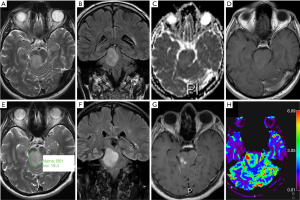

An overview of conventional imaging features is shown in Table 3. All H3 K27M-mutant gliomas were in contact with the brain midline (Figure 3). The lesion volumes ranged from 9.2 to 103.1 cm3. The definition of the non-contrast enhancing tumour margin appeared variable, whereby most lesions demonstrated heterogeneous T2/FLAIR signal. The observed T2/FLAIR heterogeneity corresponded to visible differences in ADC signal, with facilitated diffusion shown in necrotic glioma components. None of the H3 K27M histone-mutant gliomas exhibited a T2-FLAIR mismatch sign. Several tumours contained haemorrhagic components (Figure 4), whereas calcification was not identified, and only two tumours contained cysts. Rim-enhancement surrounding necrosis was present in 10/15 (67%) gliomas; 6/15 (40%) patients required shunting for hydrocephalus. Two gliomas were imaged with dynamic susceptibility contrast enhanced (DSC) perfusion MRI (Figure 5), which revealed elevated relative cerebral blood volume (rCBV) indicative of neovascularity. In one case, 18F-choline PET imaging was performed, showing radioactive tracer accumulation within enhancing tumour components (Figure 6).